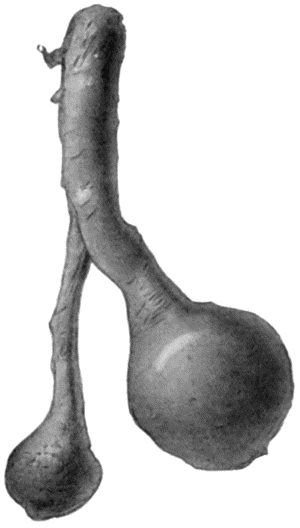

| 167. | Loose Body from Knee-joint | 541 |